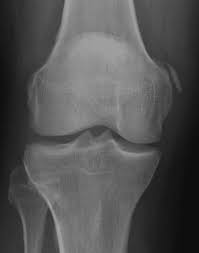

Pellegrini stieda syndrome is a medical problem which is characterized by pain, swelling and inflammation in the knee. It is a common incidental finding on knee radiographs. Pain and restriction of movements. The cause of the knee effusion is unknown. There is a moderately large knee effusion. The diagnosis pellegrini stieda disease was made. Is the presence of a radiological finding of calcification on the medial side of the knee as a consequence. It is likely that this patient has been an active sportsman in the past.

Pain and restriction of movements. The cause of the knee effusion is unknown. It is likely that this patient has been an active sportsman in the past. #foamed #foamrad #radiology #rad #elearnrad #voxelz #varunbabu #drbabu. Pellegrini stieda syndrome is a medical problem which is characterized by pain, swelling and inflammation in the knee. Most of the cases of pellegrini stieda lesions are not symptomatic, and pellegrini stieda syndrome is said to exist when the lesion becomes symptomatic i.e. Ayurvedic treatment is the natural way to treat pellegrini stieda syndrome. Is the presence of a radiological finding of calcification on the medial side of the knee as a consequence. The diagnosis pellegrini stieda disease was made. It is a common incidental finding on knee radiographs. With the ayurvedic treatment, it is possible to avoid surgery. This occurs due to the deposition of calcium on the inner side of the knee. Learn about this soft tissue calcification around the knee joint.

Pellegrini stieda syndrome is a medical problem which is characterized by pain, swelling and inflammation in the knee. The diagnosis pellegrini stieda disease was made. Learn about this soft tissue calcification around the knee joint. The cause of the knee effusion is unknown. There is a moderately large knee effusion. Pain and restriction of movements. Is the presence of a radiological finding of calcification on the medial side of the knee as a consequence. It is a common incidental finding on knee radiographs. Most of the cases of pellegrini stieda lesions are not symptomatic, and pellegrini stieda syndrome is said to exist when the lesion becomes symptomatic i.e. #foamed #foamrad #radiology #rad #elearnrad #voxelz #varunbabu #drbabu. It is likely that this patient has been an active sportsman in the past. There is evidence of osteoarthritis. This occurs due to the deposition of calcium on the inner side of the knee.